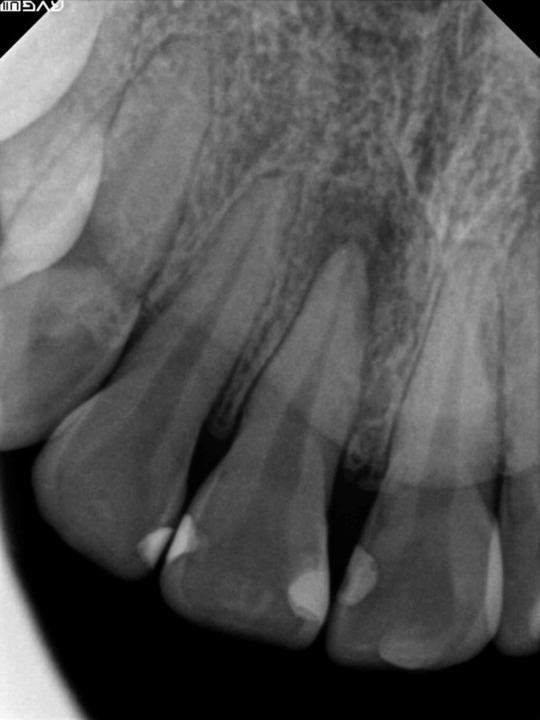

症例3

フィステル(瘻孔)があって、変色している症例。根管治療をすると、フィステルは消失。

レントゲン写真がこちら。根管治療&根管充填(この場合キャナルス&ガッターパーチャ)後。